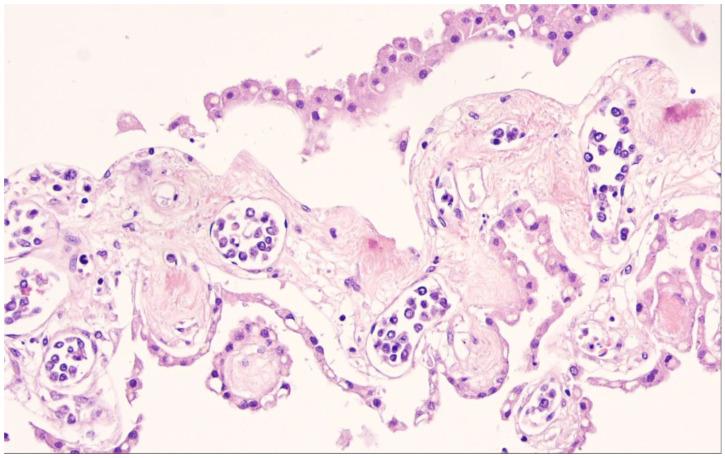

The family/class of the large B-cell lymphomas (LBCL) in the 5th edition of the World Health Organization (WHO) classification of haematolymphoid tumors (WHO-HAEM5) features only a few major changes as compared to the 4th edition. In most entities, there are only subtle changes, many of them only representing some minor modifications in diagnostic terms. Major changes have been made in the diffuse large B-cell lymphomas (DLBCL)/high-grade B-cell lymphomas (HGBL) associated with and and/or rearrangements. This category now consists of and rearranged cases exclusively, while the double hit lymphomas now constitute genetic subtypes of DLBCL, not otherwise specified (NOS) or of HGBL, NOS. Other major changes are the conceptual merger of lymphomas arising in immune-privileged sites and the description of LBCL arising in the setting of immune dysregulation/deficiency. In addition, novel findings concerning underlying biological mechanisms in the pathogenesis of the different entities are provided.

在世界卫生组织(WHO)血液淋巴系统肿瘤分类第5版(WHO-HAEM5)中,大B细胞淋巴瘤(LBCL)家族/类别与第4版相比仅有一些主要变化。在大多数实体中,只有细微变化,其中许多仅代表诊断术语上的一些小修改。在与 和 以及/或者 重排相关的弥漫性大B细胞淋巴瘤(DLBCL)/高级别B细胞淋巴瘤(HGBL)方面有重大变化。这一类别现在仅由 和 重排的病例组成,而 双打击淋巴瘤现在构成DLBCL、未另行特别说明(NOS)或HGBL、NOS的基因亚型。其他主要变化包括免疫豁免部位发生的淋巴瘤在概念上的合并,以及免疫失调/缺陷情况下发生的LBCL的描述。此外,还提供了关于不同实体发病机制中潜在生物学机制的新发现。